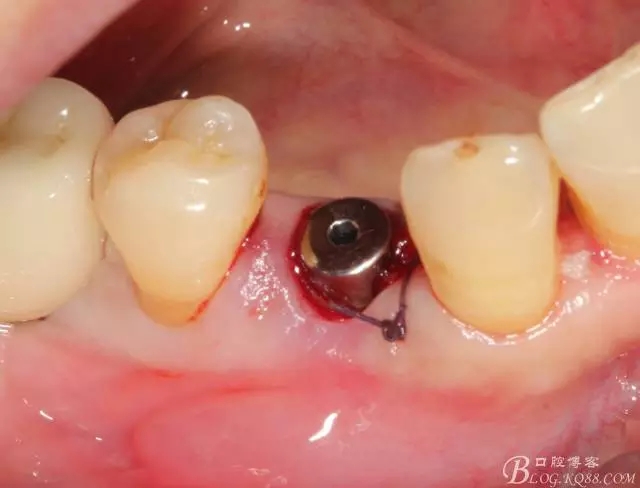

簡單備洞以后植入種植體 植體和頰側(cè)空間距離大于2毫米 注意沒有植骨

這個角度更能看到植體與頰側(cè)骨壁的空間了

適當(dāng)塞入膠原塞 簡單縫合